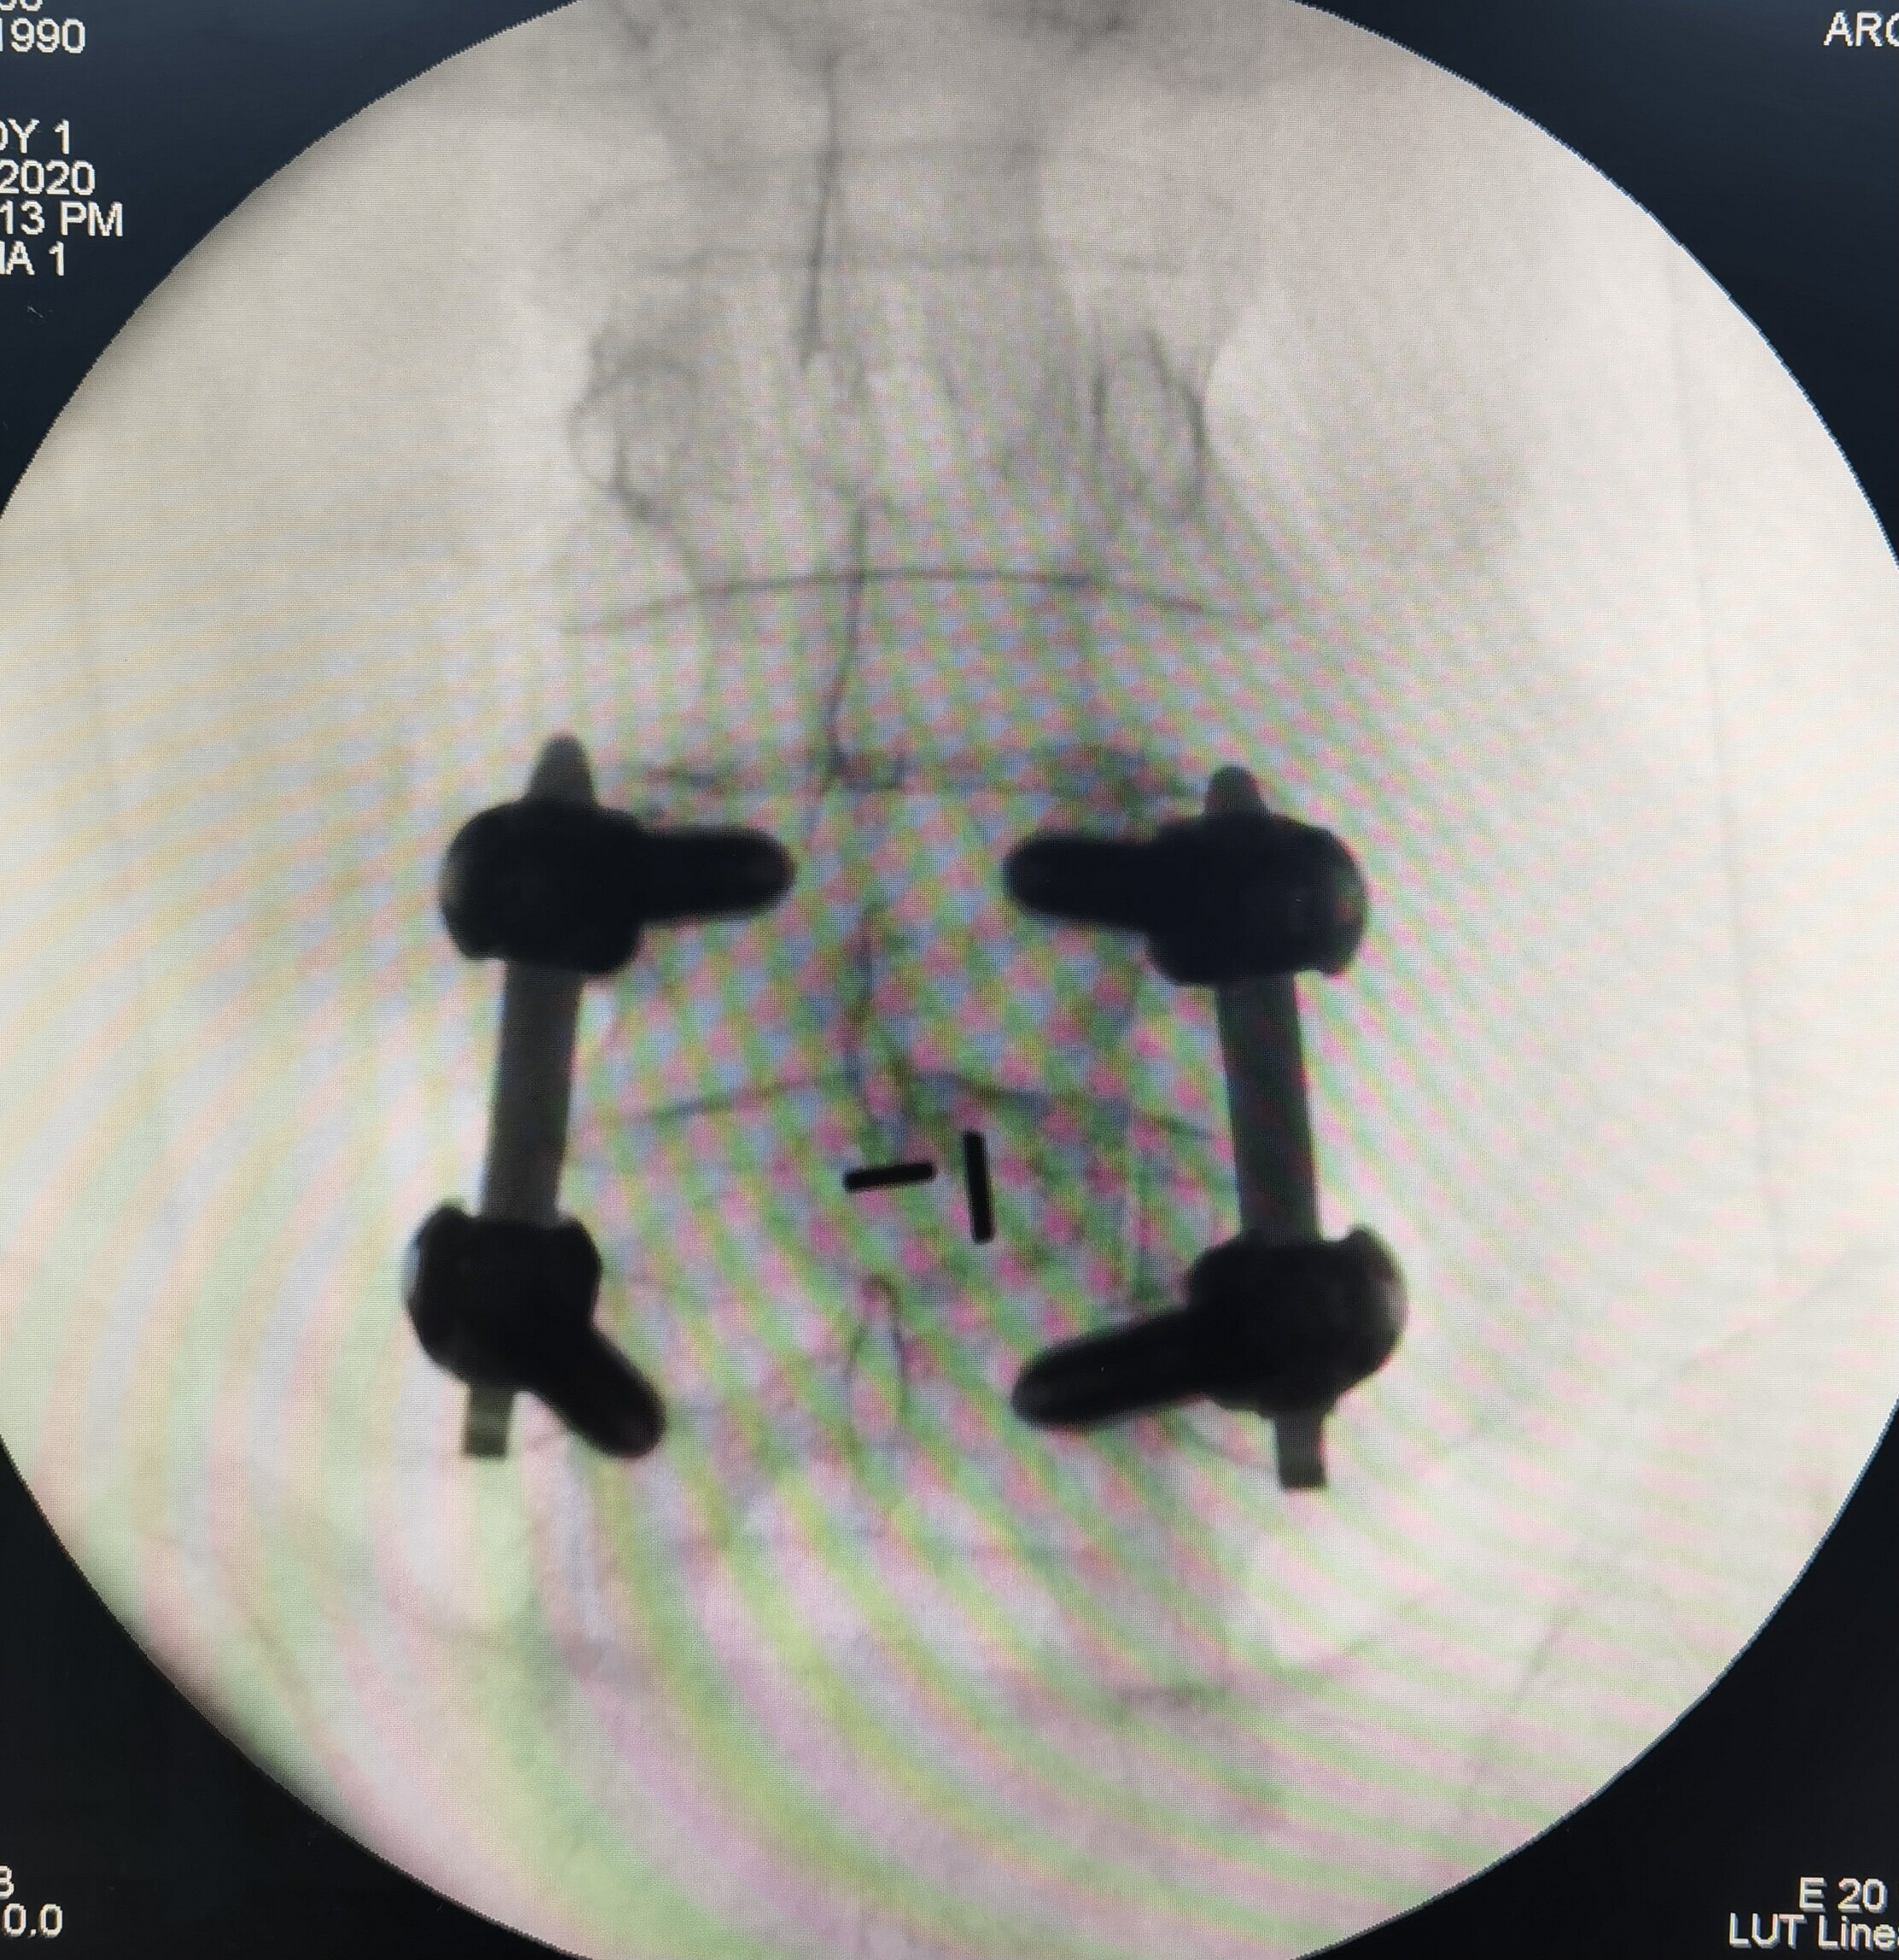

微创内窥镜治疗腰椎滑脱X光片的侧位透视片